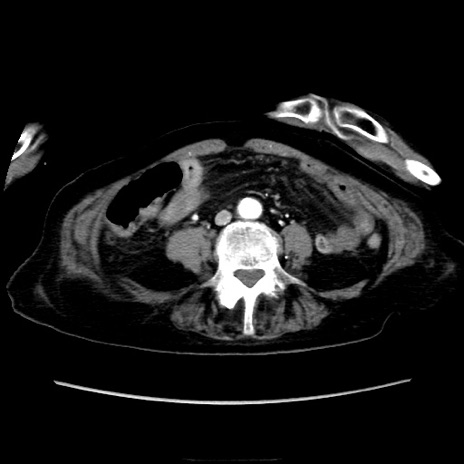

症例40(横断像)

【症例】90歳代女性

【主訴】腹痛・嘔吐

【現病歴】 食欲低下、嘔吐があり昨日他院受診。肺炎と診断され入院となる。入院後より腹部全体に圧痛あり。胃管留置され経過みていたが、症状持続するため、

当院転院となる。

【既往歴】胸椎圧迫骨折、胆石症

【身体所見】腹部:中央に激痛あり、圧痛あり、反跳痛不明

【データ】WBC 17100、CRP 18.82

横断像